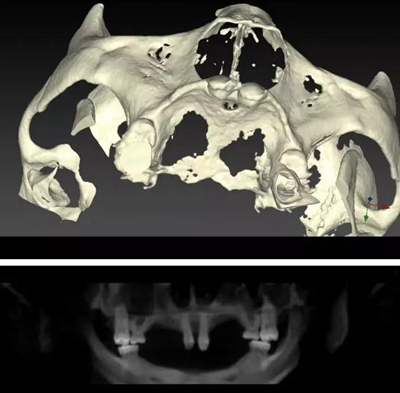

病例資料:患者,男,23歲,先天性多數(shù)恒牙缺失,影響咀嚼和美觀功能。無恒牙拔牙史,無系統(tǒng)性疾病史,身體健康,無藥物過敏史。

??茩z查:口內(nèi)僅剩16,11,21,26,雙側(cè)上下頜乳牙E滯留,其余恒牙缺失,上下頜骨發(fā)育不足,缺牙區(qū)牙槽嵴呈刃狀,上下頜弓比例協(xié)調(diào)。CBCT顯示:上頜前牙區(qū)牙槽嵴寬度約2-3mm,骨高度約10mm;上頜后牙區(qū)可用牙槽骨高度僅1-2mm,左右側(cè)上頜

竇內(nèi)粘膜有明顯增厚。下頜牙槽骨寬度及高度嚴(yán)重不足,僅存有基骨。